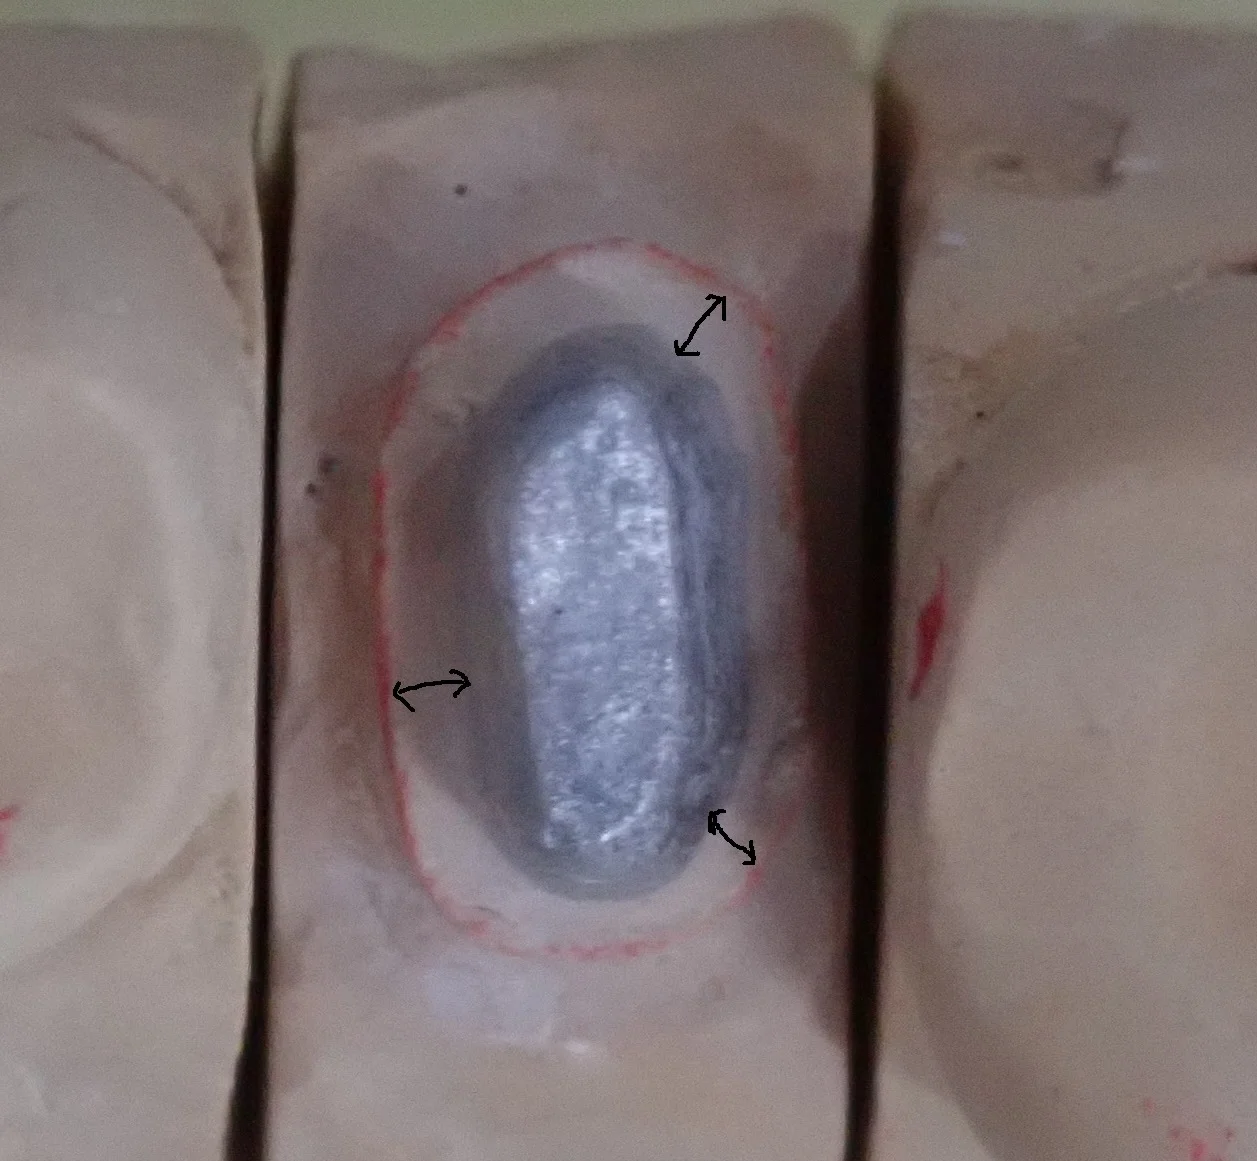

歯肉縁下深くに及んだ二次う蝕をダイレクトボンディングで修復

群馬県からお越しの男性歯科医師の患者さんです。右下7番 遠心の歯肉縁下深くに及ぶ二次う蝕を、ラバーダム防湿下でダイレクトボンディング修復しました。遠心エナメル質はクラックに沿って崩れたもので、感染歯質はエナメル象牙境付近に限局。良好な隔離環境を確保でき、適合の良い仕上がりが得られた症例です。